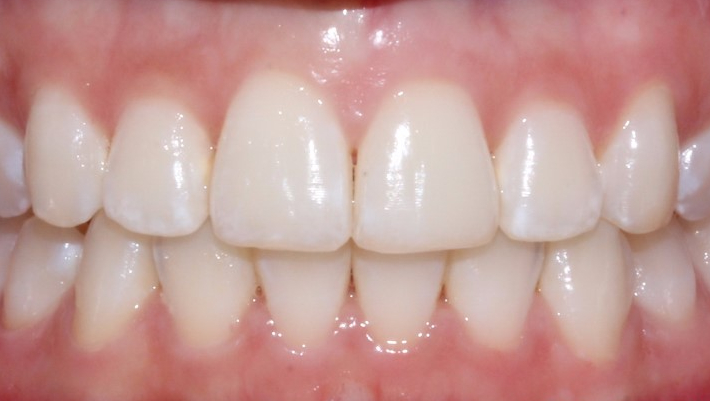

안녕하세요 ^_^

신논현역 치과, 투디치과입니다.

오늘은 앞니돌출 케이스를

부분교정으로 개선한 사례에 대해

설명해드리고자 합니다.

앞니가 조금 긴 것 같아요.

전체교정으로 하면

기간이 얼마나 걸리나요?

환자분의 치아상태를 체크해보니

앞니 공간이 부족하여

살짝 돌출되면서

비틀어진 것을 확인할 수 있습니다.

이런 경우, 부분교정으로 가능합니다.